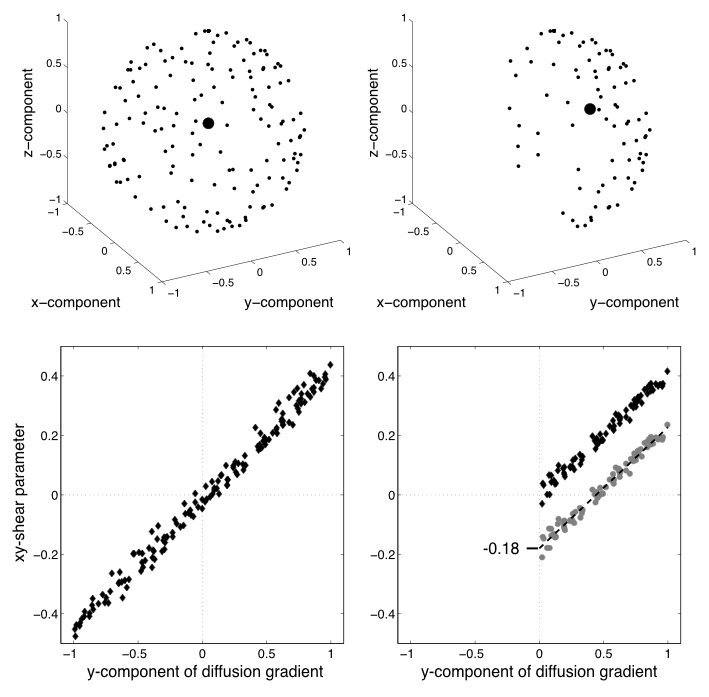

| Demonstration of unbiasing through second-level modelling. |

|---|

|

| The top-left panel shows the sampling points of a data set sampled on the whole sphere. The bottom left panel shows the estimates of one of the EC-parameters (the xy-shear parameter) plotted against the $y$-component of the diffusion gradient. It can be seen that the estimates are quite well described as a linear function of the $y$-component. The top right panel shows the sampling for the same data set, but now after having removed any volumes/directions with a negative z-component. The larger black dot shows the mean/centre-of-gravity of the different directions, and it can be seen that it has a clear non-zero component in the $y$-component. The grey circles in lower right panel shows the xy-shear estimates when eddy was run on the half-sphere data. It can be seen that the zero-point has been shifted since the "average distortion point" in the half-sphere data has a non-zero $y$-component. But by fitting a straight line to these points we get an intercept (in this case -0.18), and by adding that intercept the estimates become almost (you wouldn't expect them to be exactly identical since they only use half the data) identical to the whole-sphere case. |